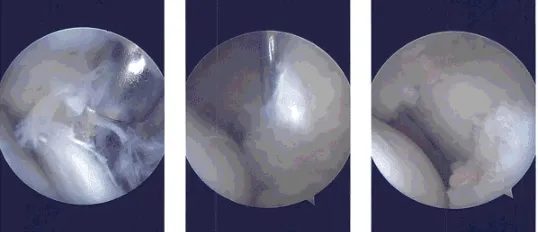

Intraoperative Arthroscopy Images

Pre antibiotics were already given. Lateral entry portal was made through the lateral incision. The arthroscope was entered and the knee was examined. It showed a tear in the anterior horn of the lateral meniscus.

On examination of the lateral compartment, there was a tear on the anterior horn of the lateral meniscus with part of the root Intact. Incision and debridement of the anterior horn was not taken as the wound was frayed.

Debridement was done using punches as well as shaver. A balanced margin was made. There was no osteochondral lesion on the lateral femoral condyle.

Upon examination of the lateral femoral condyle, there was grade 2 to grade 4 osteochondral lesions over the trochlea and the patella. Debridement of the osteochondral lesion was done using a shaver.

Chondral pick was used to do microfracture on the osseous surface of the patella at two points. The knee was thoroughly irrigated. Examination was again performed from the medial portal and balancing of the lateral meniscus was performed and confirmed.